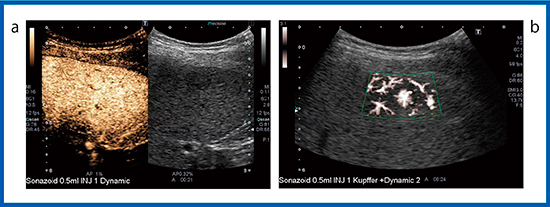

造影SMIが有用であったFNHの症例を示す(図3)。血管相(図3 a)において多血性の腫瘤が認められ,経験豊富な医師は血流が中心から周囲に向かって流れていることを理解できるが,経験の浅い医師には多血性腫瘍と見誤り,FNHと診断することが困難と考えられる。そこで,造影SMI(図3 b)を行うことにより,中心から放射状に広がる血管構築が明瞭に描出され持続的に観察でき,FNHと診断できる。FNHのように多血性で血管構築が明瞭な症例や,HCCにおけるバスケットパターンなどに造影SMIは有用である。

図3 FNHの造影SMI

a:造影超音波 b:造影SMI

図4は脂肪肝で,Bモード画像(図4 a)においてS4背側に2cm台の低エコーの結節があった。通常の造影超音波検査では描出されず,高音圧の造影SMI(図4 b)を施行すると,低エコー結節の中の血管構築が描出された。このことから腫瘤性病変ではなく右胃静脈の還流異常によるfocal spared areaであると確定診断できた。

図4 脂肪肝の造影SMI

a:Bモード b:造影SMI